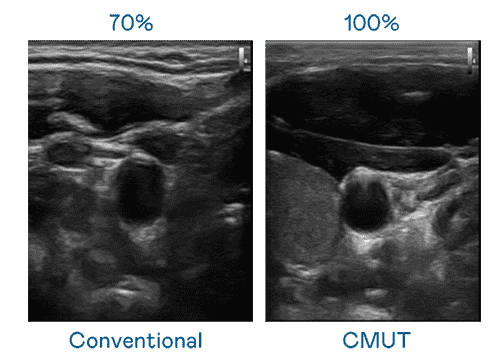

CMUT 技术是一种用电容式微机电元件来产生超音波讯号的技术。。与传统 PZT 压电式技术相比,,,,CMUT 频宽增加 30%,,,,更宽频的超音波讯号让影像解析度大幅提升,,,是实现高影像品质医疗超音波扫描、、、、促进精准医疗发展的关键技术。。。。

超音波影像的解析度高低,,,首先取决于探头能发出的讯号频宽。。。。森林舞会 CMUT 可提供高清晰的超音波讯号,,,,提供高频宽、、、、高灵敏度、、、、影像纹理细节更高的超音波影像,,,协助医护人员缩短影像判读时间及利用精准的医疗影像进行诊断。。。